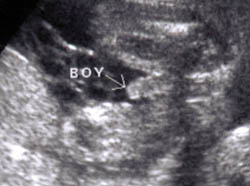

ولد في الاسبوع ال16